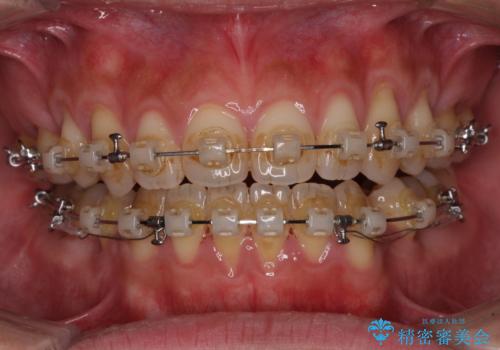

- クリアブラケット

- 2年6ヶ月

舌の突出癖を改善するためのトレーニングを指導していましたが、なかなか改善することができず、ワイヤー装置を外してからも上下前歯に隙間ができやすい状況でした。